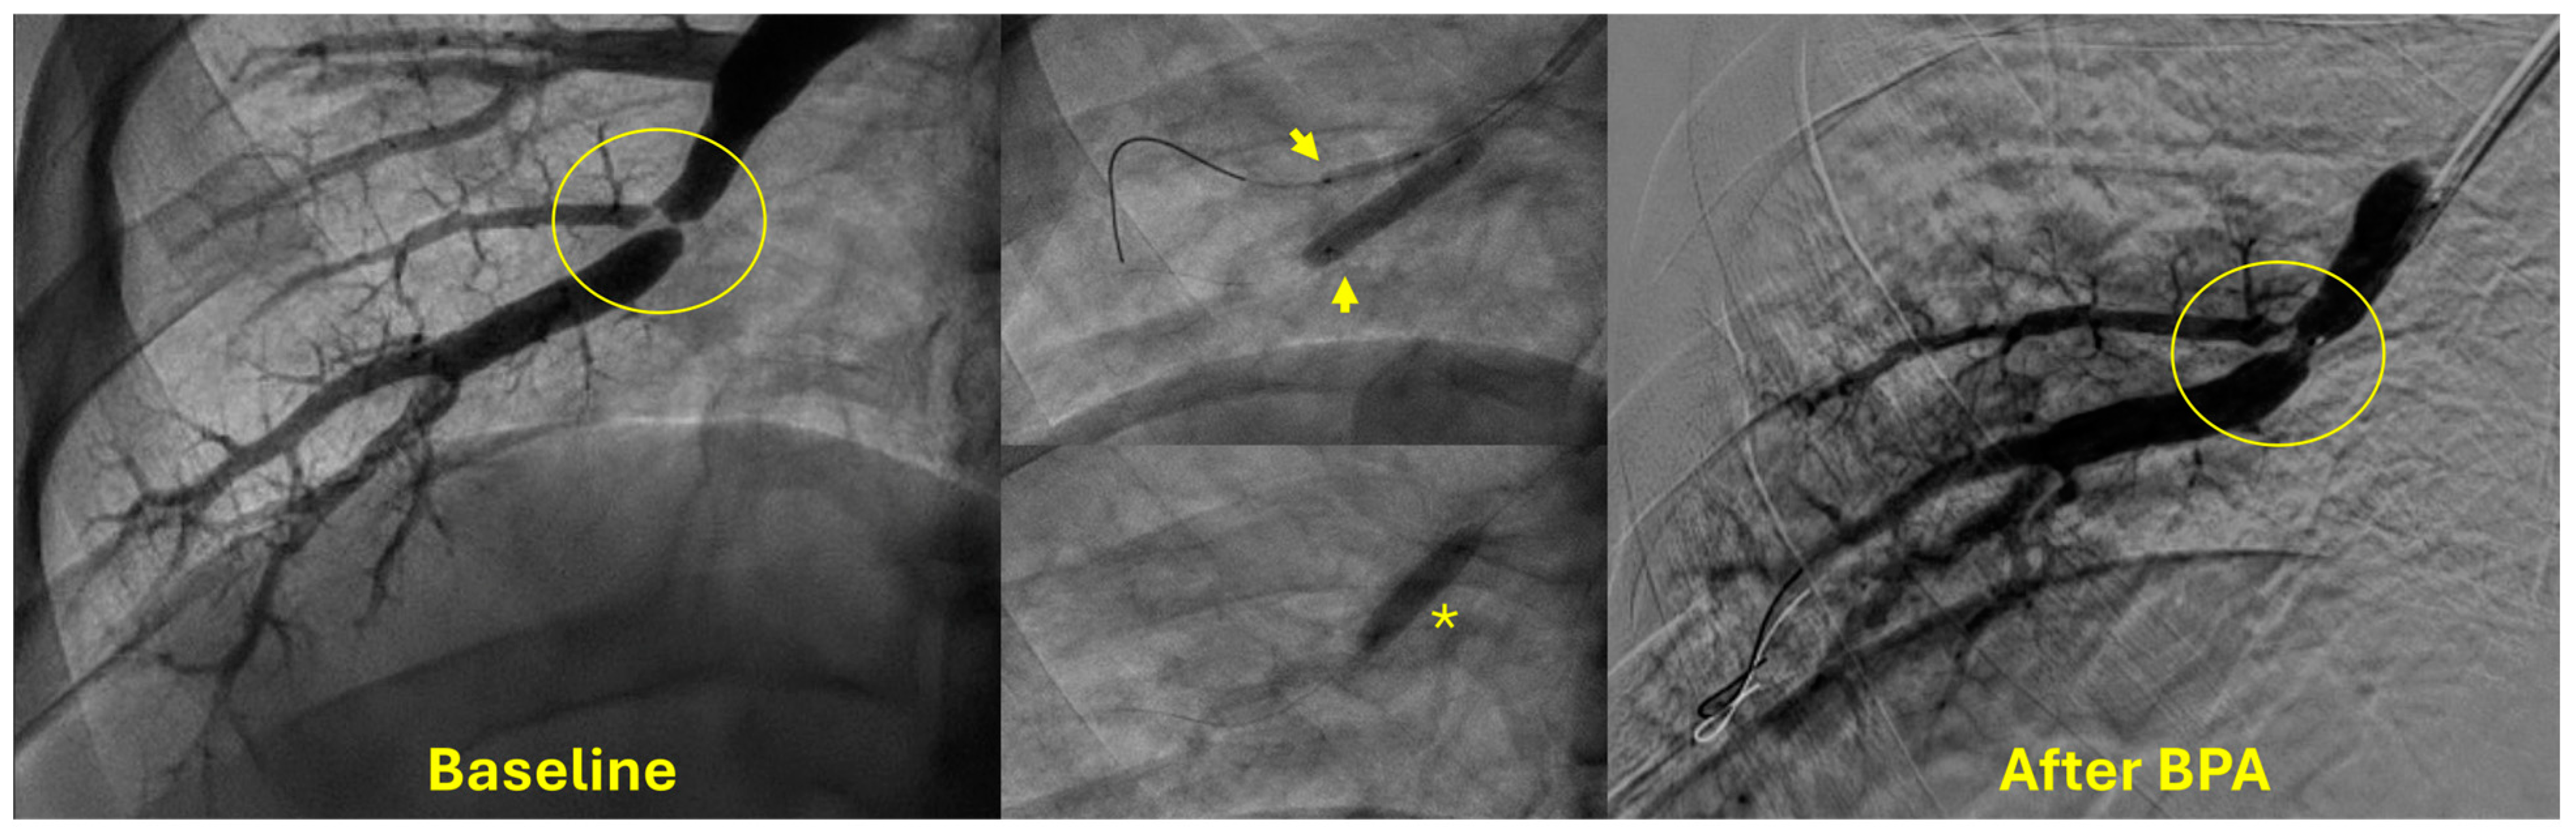

4. Indications and Patient Selection for BPA

5. Technical Considerations